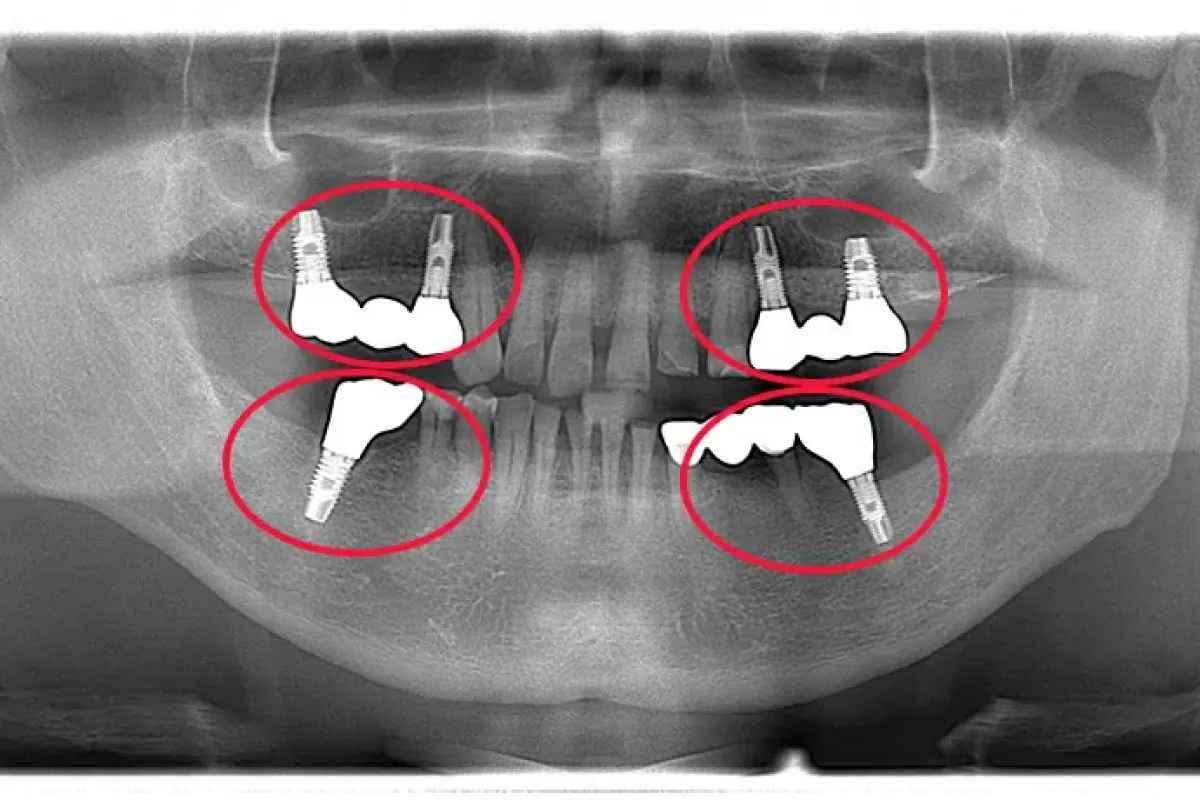

患者様情報 60代女性 患者様のお悩み 被せものがはずれた、前歯のブリッジがぐらぐらする 治療概要 虫歯治療、詰め物・被せ物、インプラント 提案内容 奥歯は金属修復補綴物の劣化、隙間からの虫歯があったので治 […]